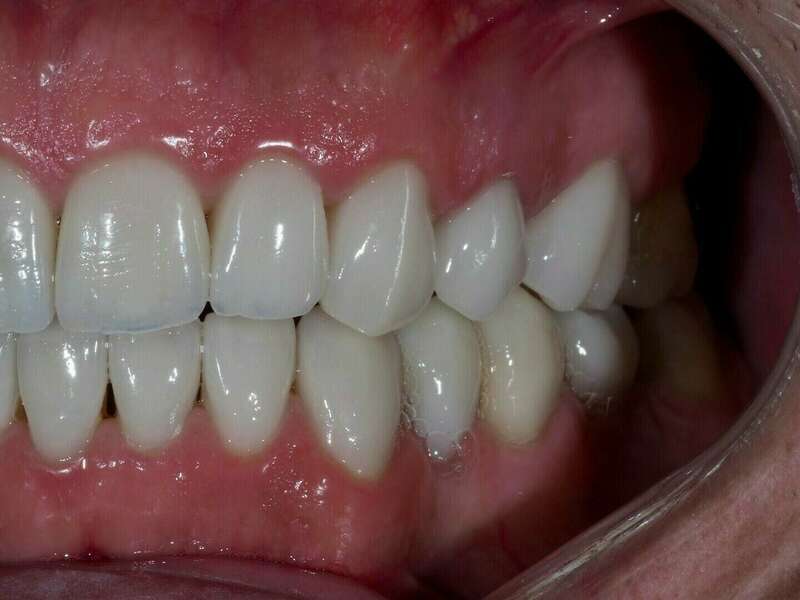

- Réalisation des couronnes ,facettes et de 3 couronnes sur implant en céramique Emax stratifiée

Après